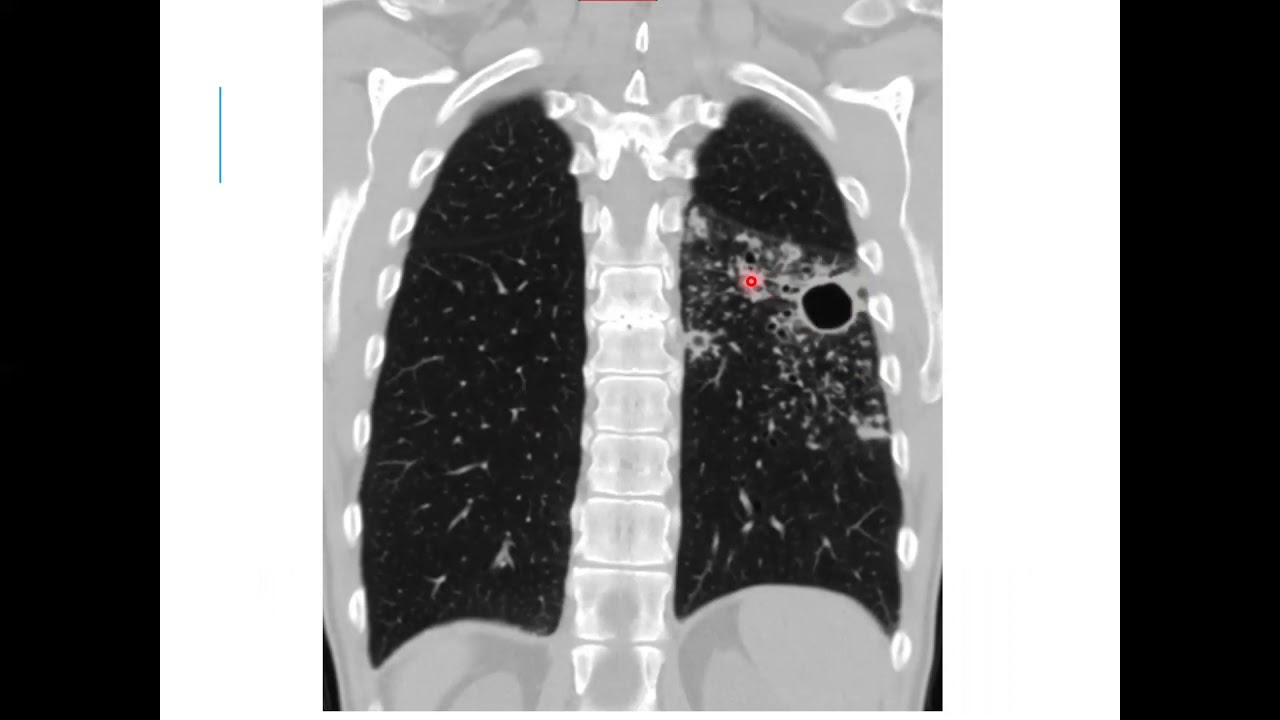

ensino primário lá né então você vai ver um paciente com escavação o seu raciocínio mais um mesmo assim meio é um paciente com ele e fala comigo Lia está assistindo não vai ser diferente né só quero explorar que às vezes a gente tem que pensar contra tuberculose é progressiva Onde tiver alterações que podem indicar progressão disseminação hematogênica acontecendo a familiar a gente vê aqui a direita né a tomografia de tórax tiveram acho que elas são bem bonitinho né com paredes bem espessadas que é o caso de voz o maior prazer Jesus as escavação né a

formação expansiva que está vendo a linha redondada ela tem paredes espessadas e no interior um palestino líquido ou não aqui tem outros dias a gente vai mais para frente aqui é uma Peça Nossa fica bonito né ele uma peça de queijo também como se é bem escavado escavação geralmente da tuberculose ela não é é regular né Ela é justamente bem regular mesmo Acontece uma necrose hialina necrose caseosa aqui na geografia e que tem que tomar um treinado Mas vocês vão pegar esse conteúdo quem tem pouca experiência você vai ver né amor Qual cidade é arredondado

aqui né no terço superior do pulmão direito ventilado superior né E aí tem um pouquinho de gás no interior dela tipo assim dúvida aí então a escavação Ela acabou de falar aqui naquele serviu para mostrar mais os casos aqui xaxá do chão pequeno tão irregular Cravinhos depois eu vou mostrar um Mônico que é se matador você não esqueça inclusive diagnósticos diferenciais de escalação de caridade a disseminação humilhar transformador gente olha só a peça é tudo que a gente vê lá na tomografia essa neste isso né parece milho Mia milhar é são os meninos ver quem